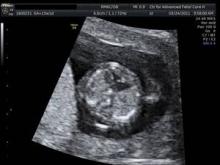

Photo courtesy Dr. Christopher Harman

Figure 4. Complete endocardial cushion defect diagnosed at 12 weeks - first trimester echo was triggered by abnormal ductus venosus alone, during routine screening.

It wasn’t long ago that second-trimester fetal echocardiography was the gold standard for any prenatal evaluation of fetal cardiac structure and function. Now, with an early and integrated screening approach that utilizes first-trimester fetal cardiac examination, we can in fact diagnose many of the most severe heart defects as early as 12 weeks of gestation. At this stage, the fetal heart is as small as the tip of the little finger.

Indeed, significant improvements in the overall computing capability of modern ultrasound equipment, in three-dimensional color ultrasonography, and in ultrasound image resolution – as well as specific new technologic developments such as tomographic imaging and spatiotemporal image correlation – have opened the door to first-trimester cardiac screening.

In the majority of patients, up to 12 parameters of fetal cardiac structure can be visualized. Each of the three segments of the exam takes only a few seconds to perform, so the actual collection of information is rapid. The technologic advances have also made the acquisition of images easier and less operator dependent. Moreover, the analysis is then performed offline, so the mother can go home afterward. Offline analysis of images also means that the ultrasound scan itself can be performed by trained sonographers at a distance from a cardiac center, with the information transmitted to the center for expert analysis.